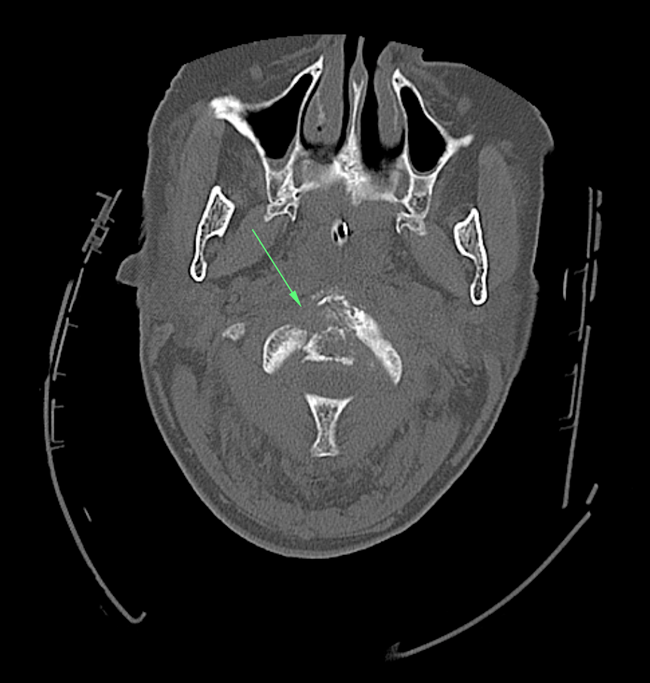

Epidural Hematoma (Pediatric)

These images were taken of a patient who had become unresponsive approximately 10 hours after falling from a deck. These coronal and axial CT images (above) show an obvious epidural bleed demonstrating the classic lentiform shape and mass-effect with a shift in the midline structures. However, there is no apparent temporal fracture as would be expected with such a finding. A craniotomy was preformed for decompression and a subsequent CT (below) shows resolution of the mass effect.